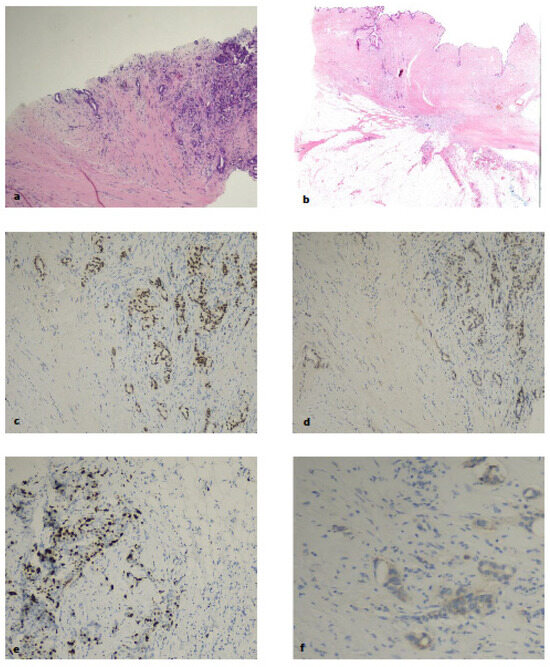

3.1. Clinically Relevant Discordances